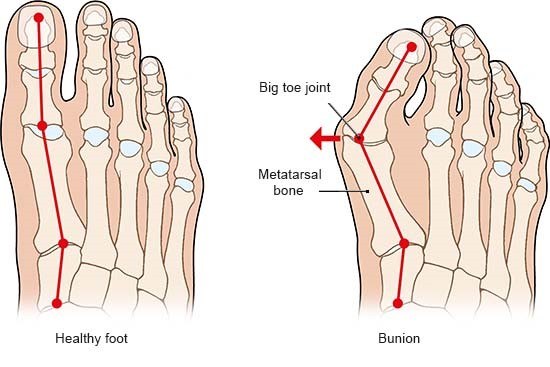

Bunion Management

The severity of the condition is assessed by an X-ray. There is no direct correlation between the size of the deformity and the degree of symptoms experienced.

The aim of the surgery is to realign the first metatarsal almost parallel to the second metatarsal. This will move the big toe back into a straight position. This is achieved by cutting the bone. Sometimes re-balancing the soft tissue around the joint or taking a small wedge of bone out of the big toe is also required (Akin). The outcome of your operation will be dependent on the quality of your joint, the degree of arthritis present. There are numerous operations to correct bunions, but essentially, they fall into two categories: transposition and rotational procedures. Transposition osteotomies include the ‘Scarf’ and the ‘capital’. Rotational procedures include the ‘Lapidus’.